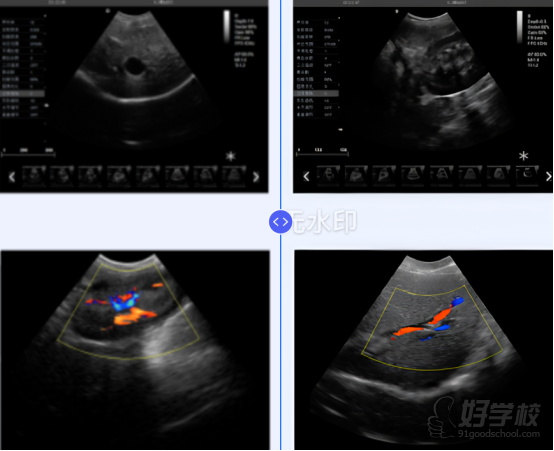

膀胱扫查:适度充盈膀胱,观察壁厚度、腔内有无异常回声,识别输尿管口尿液喷射征(彩色多普勒)。

卵巢定位:肾脏后外侧,需结合彩色多普勒寻找卵巢动脉。

模块四:血管多普勒技术与介入超声(4学时:线上1 + 面授3)

彩色多普勒:检测血流方向、速度,鉴别血管与非血管结构(如胆管与门静脉)。

频谱多普勒:测量血流速度(峰值流速、舒张末期流速),评估血管阻力指数(RI)和搏动指数(PI),用于肾血流、门静脉高压等评估。

实操练习:肾脏叶间动脉、肝门静脉、后腔静脉的血流检测。